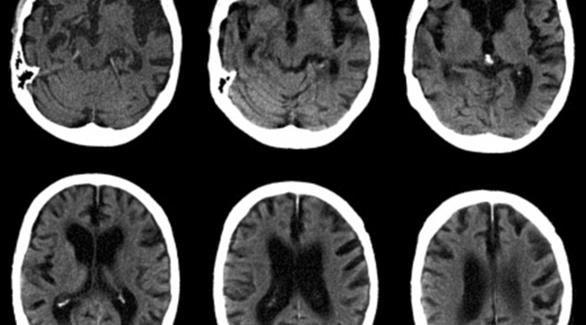

ربط باحثون من جامعة بوسطن الأمريكية بين ارتفاع نسبة الإجهاد بزيادة خطر الإصابة بالزهايمر معتبرين أن إفراز المزيد من هرمونات الإجهاد يؤدي إلى إنتاج كميات من البروتينات تسمى بمركب “تاو” بطريقة غير طبيعية.

وأفادت صحيفة دايلي ميل البريطانية أن مركب تاو الخاص بالتوتر يعيش فترة قصيرة ولكن في حالة التوتر المزمن أو طويل الأجل، يتكون تاو باستمرار ليشكل مجموعات، وهذه المجموعات تؤدي إلى ضمور الخلايا العصبية.

وأفاد الباحثون أن الإجهاد المزمن والهورمونات التي تترافق معه يمكن أن تسرع تطور مرض الزهايمر.